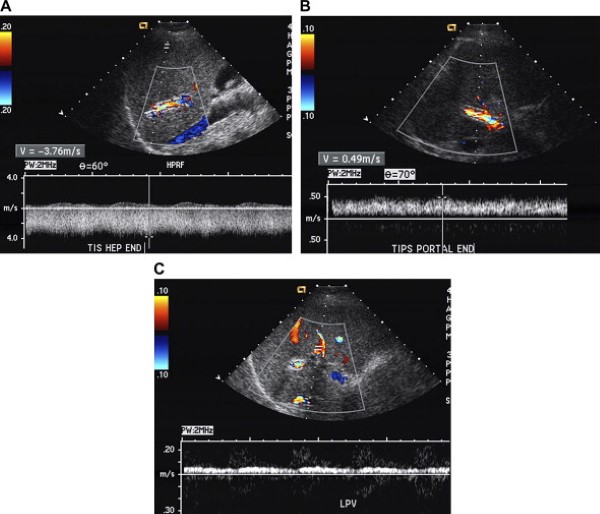

Các biến chứng của TIPS gồm có huyết khối, hẹp lan tỏa do tăng sản giả nội mạc, và hẹp khu trú, thường ở đoạn cuối tĩnh mạch gan [2].

Huyết khối stent thường chẩn đoán dễ dàng nếu hoàn toàn không có dòng chảy bên trong TIPS trên siêu âm màu hoặc năng lượng và Doppler phổ (Hình 24). Một bẫy tiềm tàng cần biết là khi thang Doppler đặt rất thấp có thể dẫn tới chản đoán dương tính giả huyết khối [27].

Hình 24. Hẹp đầu xa của TIPS ở bệnh nhân nữ 56 tuổi. (A) Ảnh siêu âm màu và Doppler cho thấy tốc độ tăng cao rõ rệt 376 cm/s ở đầu xa của TIPS. (B) Ở phần tĩnh mạch cửa (đầu gần) của TIPS. Tốc độ chỉ có 49 cm/s; sự chênh lệch tốc độ này chỉ ra sự chênh áp lớn trong shunt. (C) Dòng chảy tronhf tĩnh mạch cửa trái màu đỏ, chảy về gan, và rời xa TIPS khẳng định rối loạn shunt.

Những tiêu chuẩn đã mô tả trong y văn về chẩn đoán hẹp TIPS không được chấp nhận như nhau. Các nhóm tác giả khác nhau sử dụng các ngưỡng khác nhau với tốc độ trong stent khi đánh giá rối loạn chức năng. Tốc độ trong stent của TIPS thấp hơn 50 cm/s (khoảng giới bình thường từ 50 tới 90 cm/s) đã được coi là hẹp có ý nghĩa [27,28]. Tốc độ dòng chảy nên được đo ở cuối thì thở ra, bởi vì một nghiên cứu gần đây đã cho thấy rằng tốc độ trong TIPS giảm đến mức xấp xỉ 22 cm/s trong khi hít vào sâu [28].

Nếu có hẹp khu trú, người ta có thể thấy một vùng tăng tốc có chảy rối khu trú tại vị trí hẹp (xem Hình 24). Giới hạn trên của khoảng bình thường là từ 185 đến 220 cm/s, Middleton và cộng sự đã gợi ý ngưỡng 190 cm/s là tốc độ đỉnh tối đối với song Doppler xung đã chỉ góc [27].

Rối loạn chức năng của TIPS cũng dẫn tới giảm tốc độ trong thân tĩnh mạch cửa, với Middleton và cộng sự [27] đặt 30 cm/s là ngưỡng thấp của giới hạn bình thường [27]. Dòng chảy về gan ở nhánh tĩnh mạch cửa phải hoặc trái, rời xa TIPS khẳng định chẩn đoán [27].